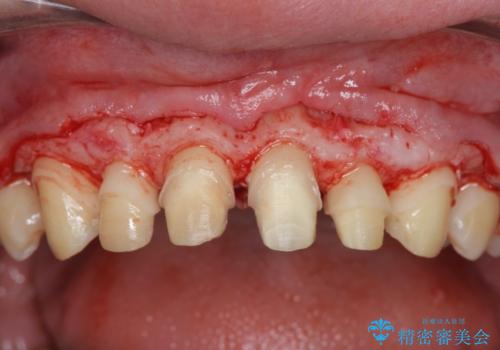

ただ、白いオールセラミッククラウンを製作・装着するのではなく、将来にわたり安定した状況を獲得するため、歯周外科を行い歯ぐきと周囲の歯槽骨の形態を整えていきます。

歯周外科を行ったことで、歯ぐきの形態や腫れが改善され、審美性だけでなく清掃性も大きく改善することができました。